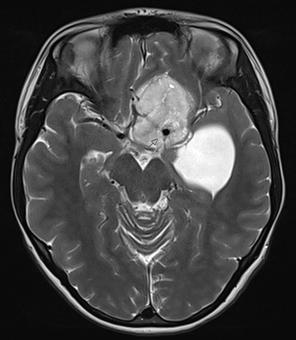

GLIOBLASTOM

Glioblastom er den vanligste formen for høygradig gliom og utgjør rundt 90 % av alle grad 4-gliomer hos voksne (Figur 1). Den aldersjusterte insidensen i Norge er 5,3 per 100 000 personår, med 251 nye tilfeller i 2024 (1). Median alder ved diagnose er 64 år, og sykdommen forekommer noe hyppigere hos menn. Standardbehandlingen har vært uendret siden 2005 og består av maksimal kirurgisk reseksjon, etterfulgt av konkomitant behandling med stråling og det alkylerende legemiddelet temozolomid, og deretter adjuvant temozolomid (5). For yngre pasienter som gjennomgår full behandling er median overlevelse 15 måneder med en toårs overlevelse på 27% (5). Norske populasjonsdata har bekreftet disse tallene, men viser at median overlevelse i en uselektert populasjon er rundt 12 måneder og toårs overlevelse 17% (6). Prognosen påvirkes av pasientens funksjonsstatus, alder, behandlingsintensitet og MGMT-metyleringsstatus, der sistnevnte indikerer respons på behandling med temozolomid (5,7). Siden introduksjonen av kjemoterapien temozolomid i 2005 er det ikke innført noen nye behandlingsmodaliteter. Likevel har overlevelsen gradvis bedret seg, der forbedringer i den kirurgiske behandlingen trolig har spilt en sentral rolle (6).

1. Til venstre: peroperativt bilde av malign og ekspansiv tumor med rik neovaskularisering. Til høyre: utdrag av MR (T1-serie med kontrast), som viser omfanget av tumor i hjernen. Kontrastladende del av tumor (CE) har vært det etablerte målet for reseksjon, men er nylig blitt erstattet med et mål om supramaksimal reseksjon som også omfatter ikke-kontrastladende tumor (nCE). Området for motorisk kontroll av høyre hånd er også markert (M).